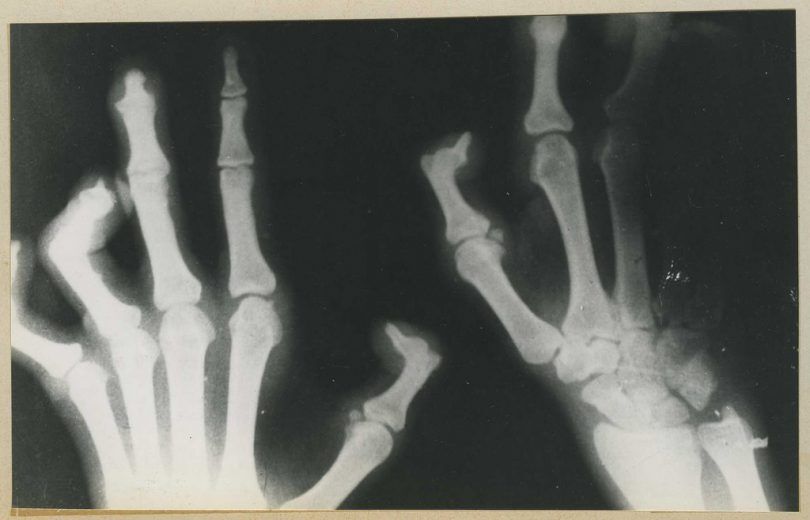

عکس رادیولوژی از انگشتان دست یک مبتلا به جذام

استخوانها بر اثر بیماری دچار خورهگی شدهاند